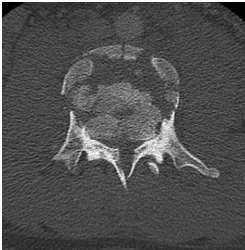

Un chico de 18 años se cayó desde tres pisos. Pérdida casi total de todas las funciones neurológicas por debajo del nivel de lesión con afectación casi total del intestino y la vejiga

El paciente fue operado y el conducto espinal limpiado de todos los fragmentos óseos. La columna vertebral se fijó de lado y la parte trasera para eliminar la inestabilidad.